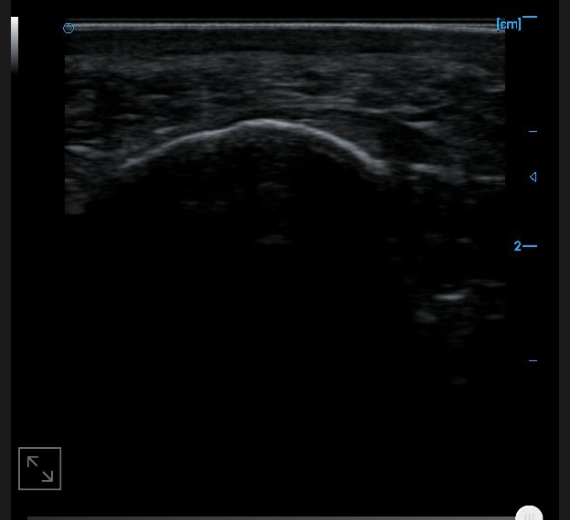

Image of anterior tibiofibular ligament B

Image of anterior talofibular ligament B

Image of plantar aponeurosis B

B image of toe and flexor digitorum tendon